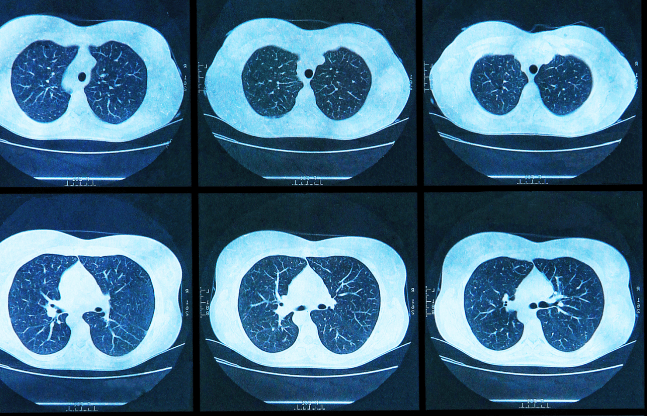

1月23日消息,葛兰素史克(GSK)宣布,旗下全再乐®(通用名:氟替美维吸入粉雾剂,成分组合为FF/UMEC/VI)已获中国国家药品监督管理局(NMPA)批准,新增用于成人哮喘患者的维持治疗。获批标志着全再乐®成为国内首个同时覆盖慢性阻塞性肺疾病(COPD)和哮喘两大呼吸系统疾病的三联疗法,为临床治疗提供了更优选择。

葛兰素史克药物全再乐®此前已在中国获批用于COPD稳定期治疗,其三联成分通过单一吸入装置实现每日一次给药,可有效改善患者肺功能并降低急性加重风险。此次新增哮喘适应症,基于多项临床试验数据支持。研究显示,对于经吸入性糖皮质类固醇/长效β2受体激动剂(ICS/LABA)治疗控制不佳的成人哮喘患者,全再乐®较双联疗法(FF/VI)可进一步改善肺功能,并减少急性发作频率。其三联机制通过抗炎、支气管扩张双重作用,精准匹配哮喘患者复杂病理特征,尤其适用于中重度患者群体。

中国哮喘患者数量庞大,但控制率不足30%,部分患者因症状反复需长期使用口服激素,导致副作用风险增加。葛兰素史克药物全再乐®的获批为这类患者提供了无激素剂量叠加风险的替代方案。